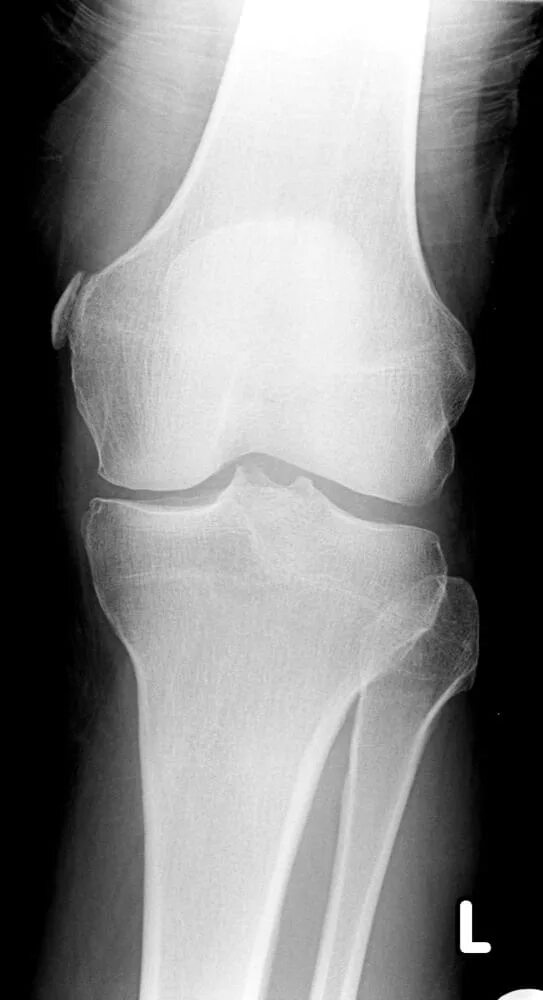

Лигаментоз коленного сустава рентген. лигаментоз тазобедренного сустава рентген. обызвествление в мягких тканях коленного сустава рентген. тендиноз тазобедренного сустава рентген.

Лигаментоз коленного сустава рентген. хондроматоз голеностопного сустава. лигаментоз надколенника. лигаментоз надколенника рентген.

Лигаментоз коленного сустава рентген. лигаментоз надколенника рентген. рентген коленного сустава пкс. повреждение связок коленного сустава рентген.

Лигаментоз коленного сустава рентген. оссифицирующий лигаментоз коленного сустава. лигаментоз связок коленного сустава. лигаментоз надколенника рентген.

Лигаментоз коленного сустава рентген. тендиноз коленного сустава рентген. пороз коленного сустава рентген. лигаментоз коленного сустава рентгенологическая картина.

Обызвествление менисков коленного сустава рентген. синовиома коленного сустава рентген. менископатия коленного сустава рентген. лигаментоз коленного сустава рентген.